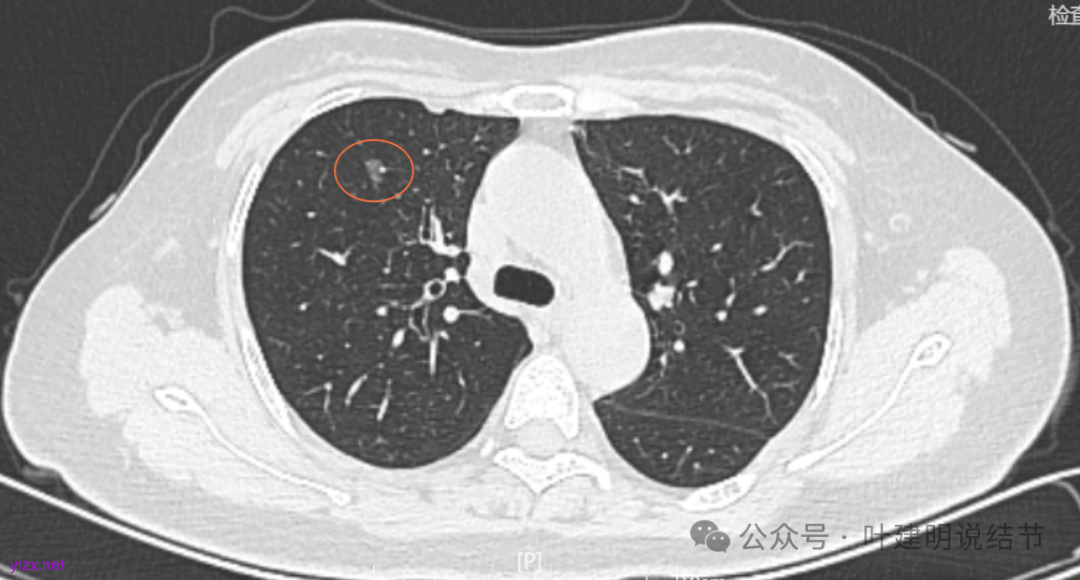

两肺多发结节,持续存在,总体上看,瘤肺边界清,轮廓清楚,主病灶有血管穿行,表面也不平,考虑微浸润性腺癌可能性大,其他2处不典型增生或原位癌可能性大些。总的来说,风险还不大,也不会引起胸痛症状,但因两侧都有,且可能后续均是要手术的,个人觉得左侧病灶可以考虑先切除,因为两个病灶离得不远,总的来说还是靠边缘的,定位后楔形切除能将两处都切了。这样只需再关注右侧的,以后真右侧也要手术,也可拉长两次手术的间隔时间,有利于恢复以及耐受性会好些。两侧同时手术,疼痛、咳嗽、恢复情况容易差些,也容易合并肺炎或其他并发症,安全性差一点的。以上意见供参考!

两肺多发磨玻璃结节,主病灶混合密度且有小血管进入,表面不平有毛刺,考虑微浸润性腺癌或浸润性腺癌可能性大,其余部分考虑原位癌或微浸润性腺癌,部分考虑肺泡上皮增生或不典型增生可能。总体上对比2022年说不上太明显的进展。但对于是否手术来讲,我仍倾向当年的意见,左侧的可以考虑近期亚肺叶(个人倾向楔切)切除,右侧的先随访,以后有进展并风险增加再考虑干预处理。因为要拉长两次手术的间隔,这样对机体的创伤与恢复更加有利一些。若定要仍不开刀,则建议要4-6个月复查,不过个人不太主张过于保守随访,对于像主病灶这种有少许实性成分的,不能保证肯定安全。意见供参考!

多发结节的处理到底该积极还是该保守,保守又该保守到怎样的程度?这真说不清楚。按既往经验,左上的混合密度结节应该是有一定风险的,既有毛刺,也有血管,还是偏实性成分,但它三年了,硬仍是几乎说不上明显进展。如果三年前按我的意见做了手术,是不是也是切早了呢?现在我仍建议她左侧的切了,是不是真的最合适的呢?其实我也不知道!因为我们对磨玻璃肺癌的认识仍很肤浅,对病因、发展以及如何处理仍在摸索之中。但从此例至少我们能得出的经验是:影像上考虑微浸润性腺癌且密度不太纯,或即使有微血管与毛刺征,仍不定会短期内进展。但是要说以此就得出结论以后类似影像表现的都不需要手术,仍可观察,或许也还是不一定正确的。我想医患双方仍得在不断的权衡与利弊分析当中选择自己想要的方案来随访或干预,基于当时的认知与知识面,基于当时的专家共识与指南,基于医生的临床经验与多学科讨论的结果。医生也要不断的总结反思与追求进步。